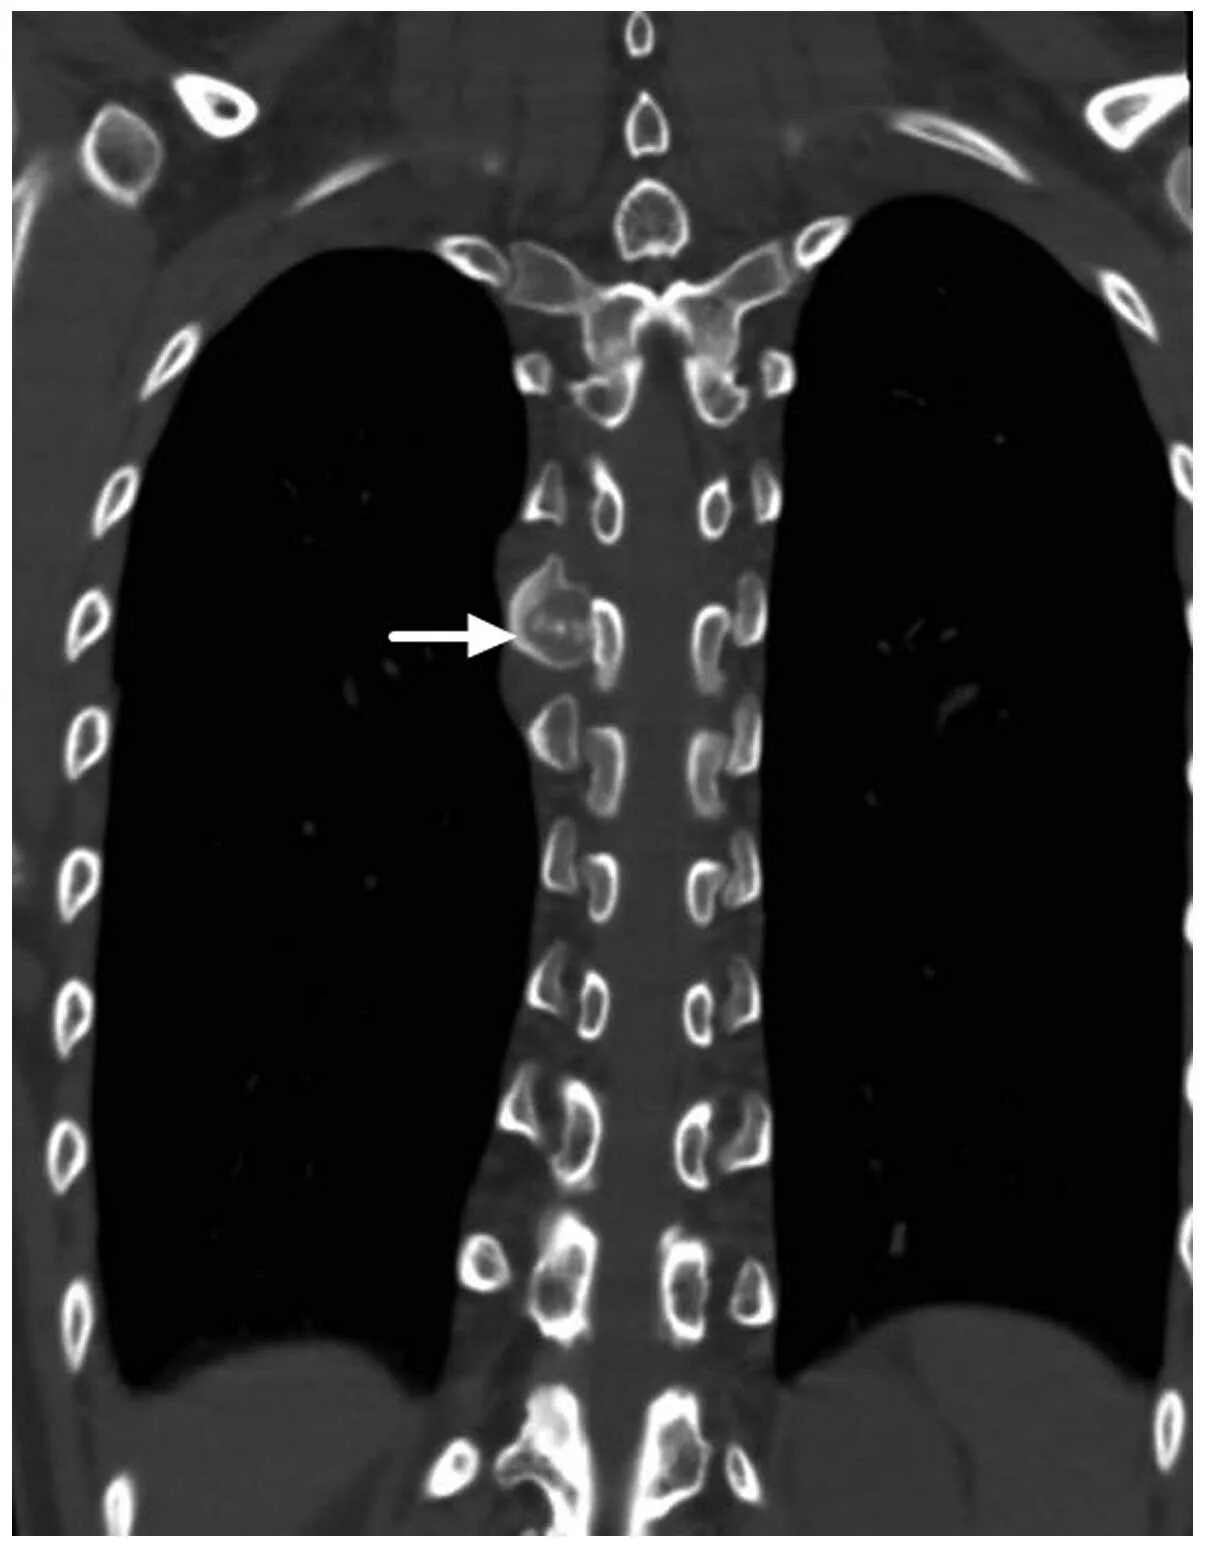

Остеосклероз грудного отдела